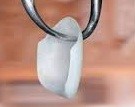

Wkład koronowo-korzeniowy wykonany z cerconu techniką CAD/CAM – spełnia taką samą funkcję jak wkład metalowy , ale daje lepszy efekt estetyczny w odcinku zębów przednich , pozwala na wykonanie korony pełnoceramicznej lub cerconowej .

Wkład koronowo-korzeniowy cerconowy.